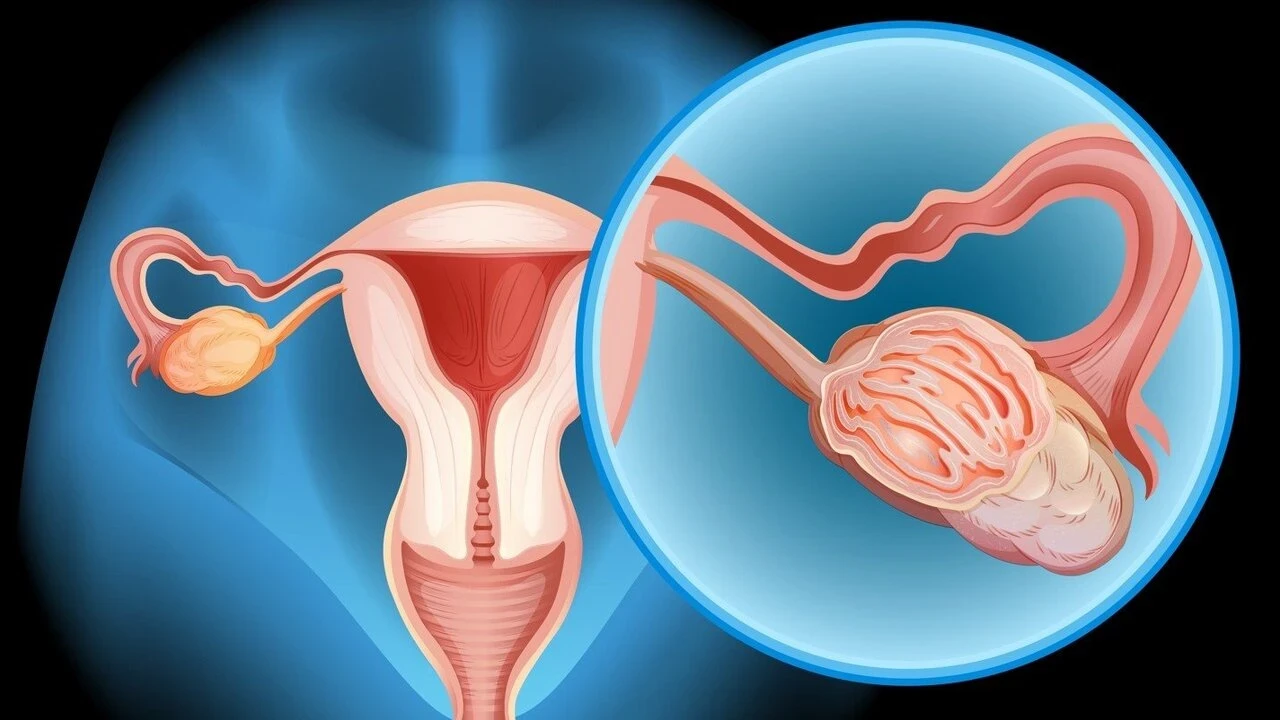

Yumurtalık zayıflığı, tıbbi adıyla primer over yetmezliği, yumurtalıkların yeterli düzeyde yumurta üretememesi ya da yumurtlama döngüsünü sağlıklı bir şekilde sürdürememesi durumudur. Bu durum, kadınların hormonal dengelerini de etkileyerek östrojen seviyelerinin düşmesine yol açabilir. Yumurtalık zayıflığı, menopozdan farklıdır çünkü bu durumdaki kadınlar hala düzensiz de olsa adet görebilir ve nadiren de olsa doğal yolla hamile kalabilir.

Yumurtalık Zayıflığı Tanısı Nasıl Konur?

Tanı koymak için genellikle birkaç farklı yöntem bir arada kullanılır:

| Test Türü | Açıklama |

|---|---|

| Hormon Testleri | Östrojen ve FSH seviyelerini ölçer. |

| Ultrasonografi | Yumurtalıkların büyüklüğünü ve folikül sayısını inceler. |

| Genetik Testler | Kromozomal anormallikleri belirlemek için kullanılır. |

| AMH Testi | Yumurtalık rezervini değerlendirmek için Anti-Müllerian Hormon testi yapılır. |